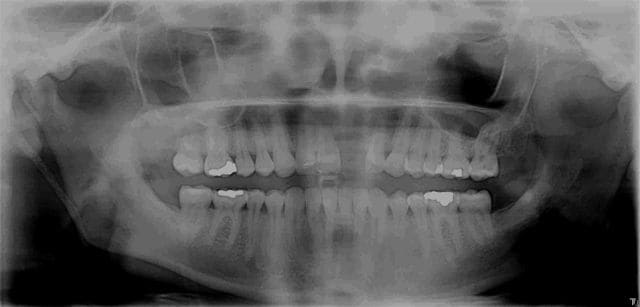

oups j'ai oublié l'OPT avant pdt et la rx après

nobel effectivement: RP Replace Groovy 4*13

Non pas speedy mais straight: apex moins agressif et implant moins compressif

J'ai eu beaucoup de craterisation avec le speedy ( surtout sur des sites anciens ) et sur une greffe je préfère la mise en place plus douce du straight pour ne pas risquer de 'décoller' le greffon cortical

P'etre bien ! Je contrôlerai ça au prochain contrôle mais sur les OPT c'est souvent trompeur